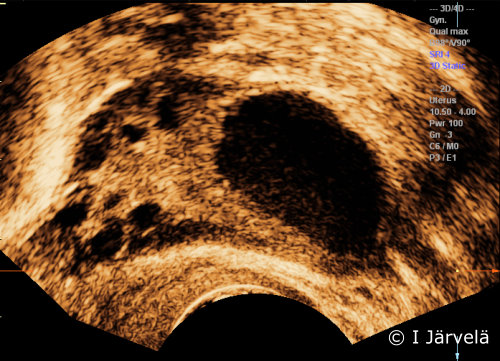

Dominant Ovarian Follicle (Ultrasound Scan)

Dominant ovarian follicle (ultrasound scan). Dominant ovarian follicle. Ovulation occurs when the dominant follicle is approx. 20-25 mm in diameter.

Picture: Ilkka Järvelä; text: Dimitrios Scordas